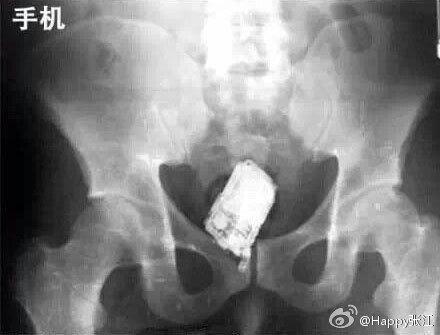

据说这是医生们盘点的肛门塞入东西的奇葩之最,毁三观啊